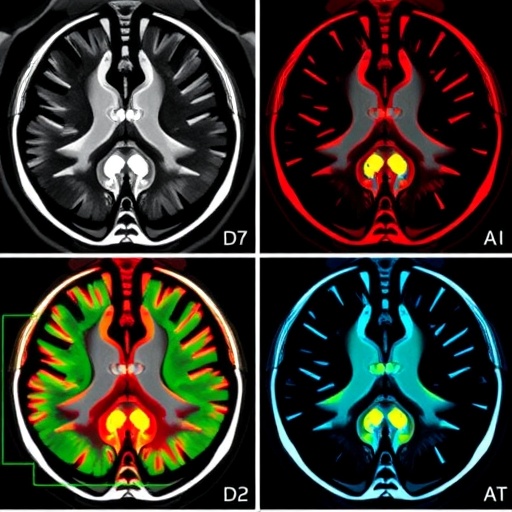

Beyond segmentation accuracy, the model excelled in minimizing relative volume difference (RVD), achieving near-ideal tumor volume quantification—critical for accurate treatment monitoring and prognosis assessment. Importantly, RST2G maintained strong generalization capabilities on external datasets acquired from clinical centers with distinct imaging protocols, underscoring its robustness and potential for real-world clinical adaptability. Visualizations produced using Grad-CAM techniques confirmed that the residual-guided attention mechanisms homed in on pathologically relevant tumor regions and boundaries, offering interpretability and fostering clinician confidence in the automated outputs.

Image Credits: Maoshan Chen, Department of Breast and Thyroid Surgery, Suining Central Hospital